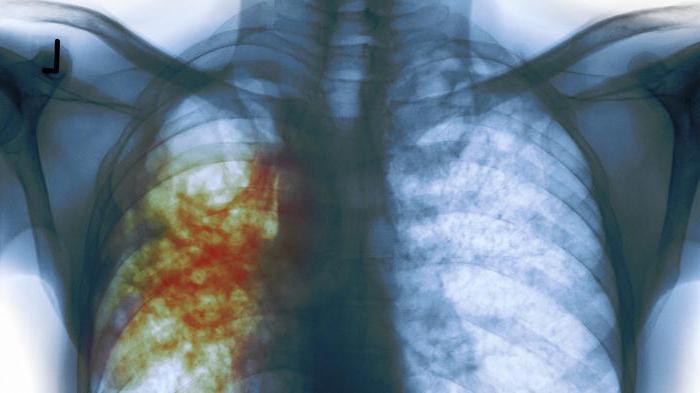

Развившийся по той или иной причине активный туберкулез может протекать в двух формах – открытой и закрытой. Об открытой форме туберкулеза (бактериовыделении) говорят в том случае, когда при помощи бактериологического исследования (посева) или микроскопии в мокроте, слюне и других выделениях больного обнаруживаются палочки Коха. Если при повторных исследованиях бактерий в выделениях нет – больной страдает закрытой формой заболевания. Термины открытая и закрытая форма туберкулеза чаще применяются для туберкулеза легких. Однако бактериовыделение характерно и для других разновидностей туберкулеза – туберкулеза лимфатических узлов, туберкулеза половой системы, туберкулеза кишечника и т.д. Наличие бактериовыделения (БК+) – очень важный показатель инфекционной опасности больного, поскольку заразиться туберкулезом можно только от человека, выделяющего микобактерии туберкулеза в окружающую среду. Однако здесь есть один нюанс: из-за недостаточной мощности лабораторных методов исследования у некоторых больных открытой формой туберкулеза микобактерии в мокроте (и прочих выделениях) обнаружить не удается. То есть, являясь, официально, незаразными, они представляют серьезную опасность для окружающих. Поэтому ни один врач не гарантирует 100%-ной безопасности людям, имеющим контакты с больными закрытой формой туберкулеза. Считается, что контакт с таким больным примерно с 30%-ной вероятностью может привести к развитию активной формы заболевания, риск заражения увеличивается при постоянном, тесном, длительном контакте.

Процесс заражения осуществляется следующим образом: в организм попадают патогенные бактерии и распространяются бронхолегочными, лимфогенными и гематогенными путями. В легких пациента формируются единичные или множественные бугорки. Туберкулез имеет две формы: закрытую и открытую. При первой микобактерии содержатся в самих бугорках, не покидая их. В этом случае больной не несет угрозы для окружающих, заразиться от него невозможно. Вторая форма крайне опасна, потому что происходит выделение возбудителя патологии вместе с мокротой.

Палочка Коха, попав в человеческий организм, поражает ткани органов дыхания или лимфатической системы. Поскольку она содержится внутри бугорка, то очаг поражения постепенно заживает, но на ткани формируется уплотнение. Это процесс представляет собой первую стадию. В случае, если инфекция попадает в кровь больного, то образуется несколько очагов поражения – так выглядит вторая стадия. Течение заболевания в этой форме не сопровождается выделением микобактерий, то есть для окружающих больной не опасен. Чтобы определить наличие патологии в организме, ее форму и стадию, необходимо пройти специальный тест на туберкулез.

- флюорография и рентген;